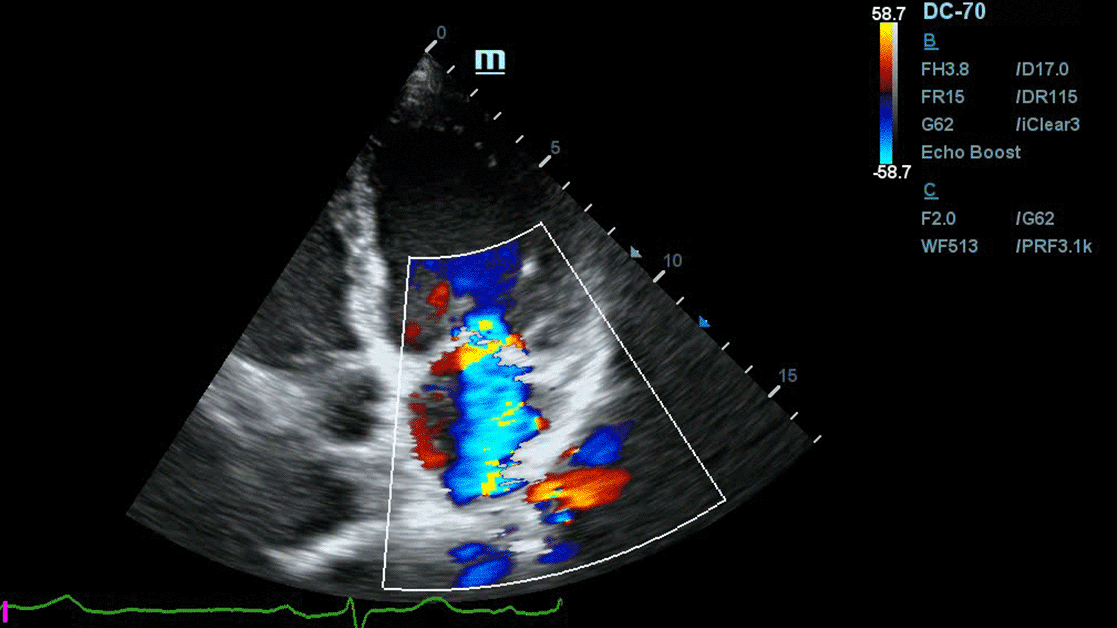

Echocardiography

Дни на Ехокардиографията 2025 | Лекция

Предизвикателството на СНзФИ, ранно иницииране на Jardiance и болест-модифициращите ползи от терапията

Проф. д-р Елена Кинова, дм

МБАЛ "Царица Йоанна - ИСУЛ", катедра Спешна медицина. МУ - София

• 12 април 2025

• София

Научете повече